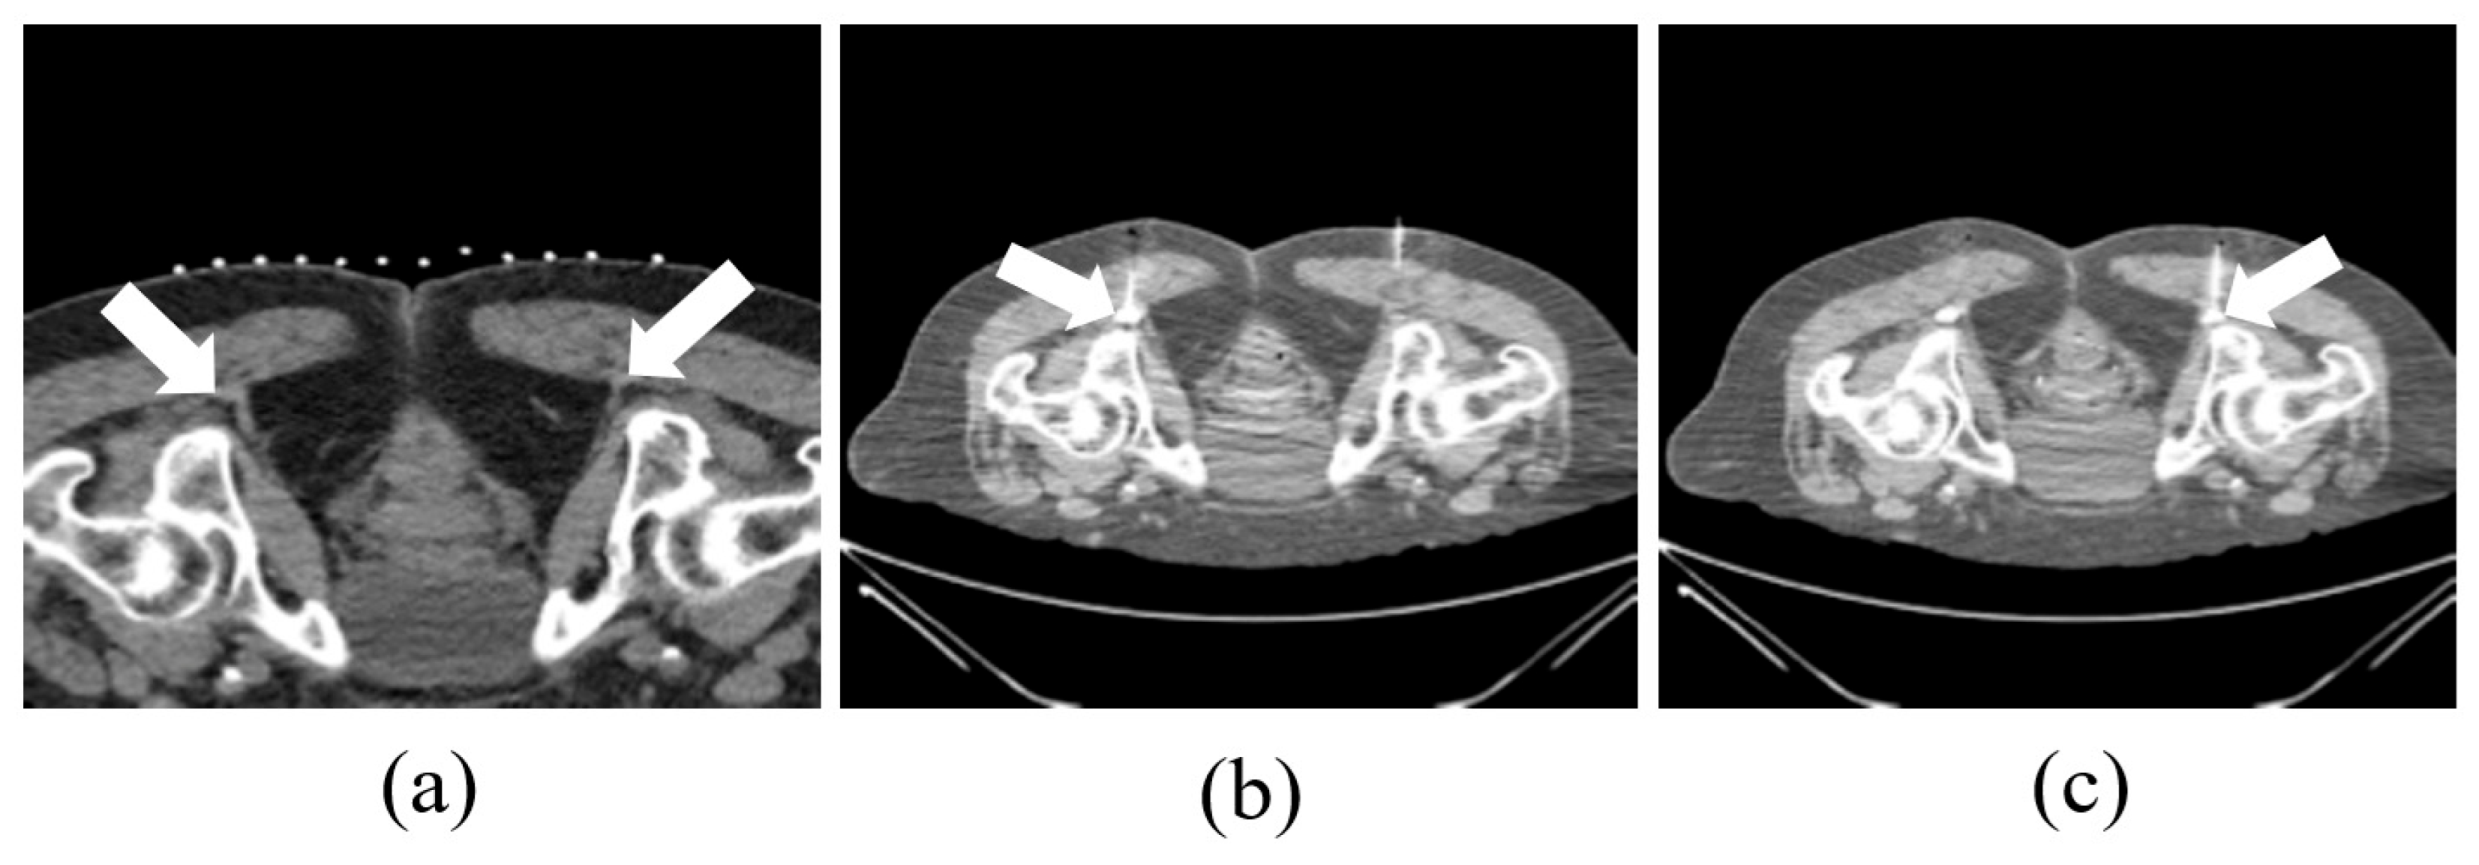

2.2. CT-Guided Procedures